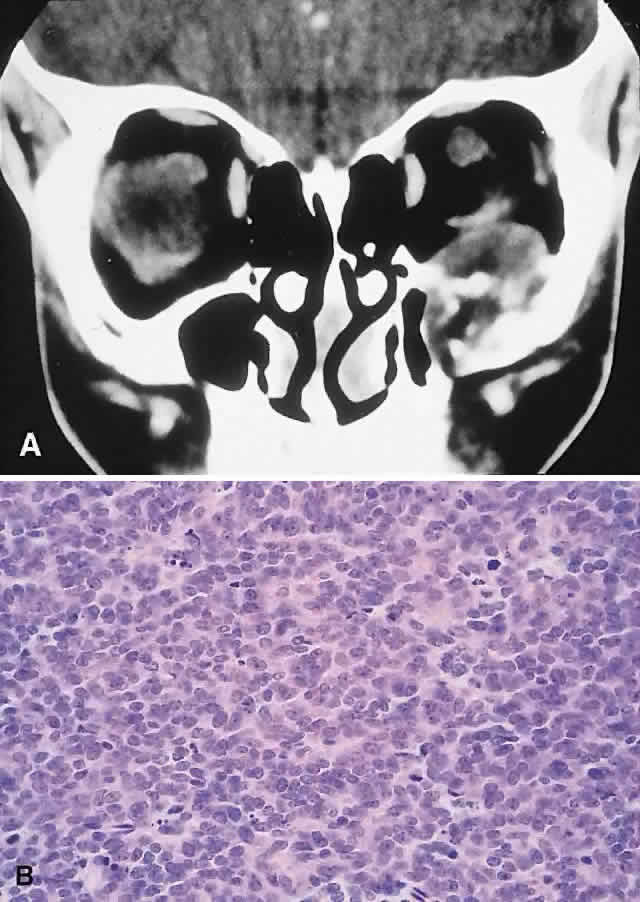

clinicopathologic classification (see Table 1). BENIGN FIBRO-OSSEOUS AND CARTILAGINOUS LESIONS Osteoma A true osteoma is a tumor-like mass of bony tissue that is histologically similar to normal bone. Its pathogenesis remains unclear, although traumatic, infective, or hamartomatous theories have been proposed.4 Others have suggested that osteomas arise exclusively at the junction of bones of cartilaginous and membranous origin.5 None of these theories account for the facts. The most common sites of origin are the paranasal sinuses, skull, and facial bone. The fact that osteomas were found in 0.42% (15 of 3510) of plain sinus radiographs reflects their prevalence.6 In the sinuses, 50% occur in the frontal sinus, with the ethmoid, maxillary, and sphenoid involved in descending order of frequency. Most orbital osteomas are secondary invaders from adjacent sinuses, but on occasion they arise primarily in the orbit. In contrast to the sinus distribution, however, orbital osteomas appear to have a roughly equal origin from the ethmoid, frontoethmoid, or frontal regions.7,8 This may reflect the relatively thin barrier to expansion posed by the medial orbital wall. The age range runs the gamut from 10 to 82 years, with the highest prevalence in the fourth and fifth decades. Males and females are represented equally.7–9 PRESENTATION. Most sinus osteomas are solitary and asymptomatic.6 However, when large enough to encroach on the orbits, a gradual evolution of proptosis or globe displacement over many years can occur (Fig. 1). There may be an associated headache as a result of expansion of the overlying cortex and periosteum, and a bony mass is often palpable in the superior or superomedial orbit. Obstruction of the sinus ostia may lead to chronic sinusitis or mucocele. Less common features include an acquired Brown syndrome,10 gaze-evoked amaurosis or pain,4,11 subluxation of the eye12 and erosion leading to orbital emphysema, or cerebrospinal fluid rhinorrhea.13 The sphenoid sinus, although a rare site, is significant because even a small lesion may lead to an orbital apex syndrome. An uncommon but important systemic association is Gardner's syndrome. This autosomal dominant syndrome of osteomas, soft tissue tumors, and peripheral congenital retinal pigment epithelial hypertrophy also includes the development of colonic polyposis with subsequent malignant transformation.14–16 Multiple osteomas are common; our one patient had only a single tumor, but one was also noted in the skull. Further, because bony lesions may predate the colonic pathology, patients with osteoma warrant a dilated funduscopy and referral to a gastroenterologist.17 IMAGING. The plain radiograph and CT appearances consist of an osteoblastic round or ovoid sharply circumscribed mass, usually arising in the sinus and invading the orbit. Tumors growing in a sinus conform to its internal contour and often have a bosselated surface. Osteomas may be sessile or pedunculated and generally have a diameter of 1 to 5 cm.18 Bone window settings on CT imaging often show a very dense periphery with a more cancellous internal structure. However, the relative proportions of the two densities may vary with the size of the lesion. HISTOPATHOLOGY. It is important to distinguish osteomas from reactive osteomatous responses to infection, trauma, and chronic inflammation. The clinical and radiologic appearances are often invaluable in this regard. Macroscopically, true osteomas have smooth or bosselated contours with a glistening white or pinkish coloration. A covering of mucoperiosteum or periorbita may be seen, depending on the site of origin.18 Osteomas have been classified histologically into three groups depending on the predominant tissue present: compact (cortical, ivory), cancellous (trabecular, spongy), and fibrous. Fu and Perzin19 have postulated that the histologic type is partly dependent on the age of the lesion, with the compact group representing the most mature and the fibrous the least. The fibrous subtype may, in fact, be part of a continuum incorporating ossifying fibroma and fibrous dysplasia. The compact areas resemble normal cortical bone with dense bony areas and haversian systems. However, there are subtle differences in the arrangement of the haversian canals, which is often evident to the experienced bone pathologist. The cancellous areas consist of anastomosing trabeculae with an intervening fibrovascular stroma. Fatty and hematopoietic elements may also be present in the stroma, as well as evidence of osteoblastic activity along the trabeculae. The fibrous region is made up primarily of loose fibrovascular tissue with a few irregular bony trabeculae and osteoid elements. In our series of nine surgically treated cases, we noted that although the three types of tissue were present in varying admixtures, in all cases there was a remarkably consistent pattern of arrangement. The most peripheral zone was made up of compact bone; moving toward the center or base of the lesion, there was an intermediate zone of increased osteoblastic activity, osteoid, and vascularity. The innermost region consisted of a loose fibrous stroma with a greater number of blood vessels, few trabeculae, and many plump osteoblasts. This configuration has been described previously by Albert and associates20 and illustrates the growth of these lesions. The outermost zone presumably represents more mature bone, and the activity seen centrally suggests that this is where growth is initiated. This implies that extirpation of the central region is probably required to prevent recurrence. It may also explain why leaving residual peripheral areas does not usually lead to regrowth. Finally, the histologic subtyping into compact, cancellous, and fibrous lesions probably has little practical significance, because there appears to be no correlation with the clinical course. MANAGEMENT. Generally, asymptomatic osteomas can be treated conservatively. The only possible exception to this is in the sphenoid sinus: it is technically easier to remove a small lesion in this location before it has encroached on the orbital apex and optic canal. If symptomatic and located in the anterior orbit, osteomas can be removed through an anterior orbitotomy. For anterior ethmoid tumors in the superomedial orbit, a modified Lynch incision is often used. Excision can sometimes be aided by coring the lesion and collapsing the cortex for removal. For more posterior tumors, involving the roof or cribriform plate, a combined orbitocranial approach using a bicoronal incision is favored.21 Recurrence is rare, even after a partial resection. Fibrous Dysplasia Fibrous dysplasia is a benign disorder in which proliferation of fibrous tissue and osteoid replaces and distorts medullary bone. The cause is unknown; past theories have included a maturation arrest at the woven bone stage, or hamartomatous proliferation.22 More recently, the discovery of a postzygotic mutation in the G protein in McCune-Albright syndrome suggests that the bone dysplasia in these patients is a manifestation of a somatic mosaic state.23,24 There are three forms of fibrous dysplasia: monostotic fibrous dysplasia (MFD), polyostotic fibrous dysplasia (PFD), and McCune-Albright syndrome.22,25 MFD accounts for 75% to 80% of cases, of which 20% affect the craniofacial bones. In the skull, the frontal bone is most commonly involved, followed by the sphenoid and ethmoid. Most patients with orbital involvement have MFD, although the disease has generally spread to contiguous bones by the time the patient comes to medical attention. PFD makes up 20% of all cases; half of these patients have head and neck involvement. McCune-Albright syndrome occurs largely in females and incorporates the triad of PFD, sexual precocity, and cutaneous pigmentation.26 This pigmentation appears as brown macules, usually six or fewer, with irregular “coast of Maine” borders.27 Fibrous dysplasia is generally recognized before age 30, although mild or asymptomatic cases may escape detection into late adult life.28 The gender distribution is roughly equal in MFD; there is a female predilection in PFD. PRESENTATION. The site and the extent of disease are the major determinants of symptomatology. Facial asymmetry, proptosis, and globe displacement evolving over many years are the most common manifestations (Fig. 2). Nasolacrimal duct blockage, diplopia, nasal obstruction, malocclusion, raised intracranial pressure, and cranial nerve palsies also occur.25,28–30 Acute or subacute compressive optic neuropathy can arise as a result of intralesional hemorrhage, sphenoidal mucocele, or secondary aneurysmal bone cyst.31 A more chronic visual loss, although less commonly reported, may occur as a result of compression in the optic canal or at the chiasm. On occasion, a superimposed ischemic neuropathy in the context of chronic compression leads to an acute on chronic deterioration in vision.32 This clinical spectrum is reflected in our experience of 10 cases. Changes in facial contour (7 patients), proptosis (7), globe dystopia (6), and decreased vision (3) were the major signs. Interestingly, seven patients also had pain, either localized to the orbit or described as a diffuse ipsilateral headache. Overall, the natural history is one of slow growth. Although this was previously thought to cease in adult life, there is evidence that fibrous dysplasia may progress well past the fourth decade.25 Rarely, malignant transformation to osteosarcoma, fibrosarcoma, chondrosarcoma, and giant cell sarcoma can occur; this is often signaled by a more rapid progression and increased pain. The incidence of this complication is estimated at 0.4% to 0.5%, rising to approximately 15% with prior radiation therapy.33 IMAGING. In the craniofacial bones, fibrous dysplasia tends to expand the bone, with thinning of the overlying cortex. The margins are poorly defined, and the dysplasia transgresses suture lines; the proportion of mineralized to fibrous tissue determines the degree of radiolucency. Most cases demonstrate a relatively equal mixture, resulting in a pagetoid appearance. Where the fibrous element is predominant, there may be cystlike areas; a preponderance of mineralized tissue, however, results in a homogeneous, sclerotic, “ground-glass” picture. Fries34 reviewed 39 patients with fibrous dysplasia of the craniofacial bones and found a pagetoid pattern to be most common (56%), followed by sclerotic (23%) and cystlike (21%) appearances. The primary differential is hyperostotic meningioma. This is distinguished by its occurrence in an older age group and by the presence of an associated enhancing soft tissue component, best seen on MRI. Also, meningioma often causes a more homogeneous thickening of bone, which in contrast to fibrous dysplasia does not leave a discernible cortical rim. MRI shows meningioma to have a signal isointense to gray matter on both T1- and T2-weighted images. Fibrous dysplasia, in contrast, tends to have a lower intensity on T1- and a heterogeneous signal on T2-weighted images.28,35 MRI may also have a role in fibrous dysplasia in the evaluation of mucoceles and recent hemorrhage. On occasion, Paget's disease and less commonly cystic bone lesions, such as localized Langerhans cell histiocytosis (eosinophilic granuloma), also enter into the differential diagnosis. Paget's disease arises beyond the age of 40, is usually bilateral, and radiologically may show areas of cotton wooltype density that are not usually seen in fibrous dysplasia. HISTOPATHOLOGY. Macroscopically, fibrous dysplasia consists of gritty, white-to-pink tissue, often with blood or serous-filled cystic areas. Histologically, there is a fibrous background containing trabeculae of woven bone. The stroma has variable amounts of collagen, fibroblasts, and vascularity. There may also be myxomatous areas and secondary aneurysmal bone cysts. The curvilinear bone trabeculae take on a variety of configurations, including C or Y shapes (so-called Chinese characters). These trabeculae sometimes have irregular margins as a result of the attachment of collagen fibers arising in the stroma. Cartilaginous nodules as well as small foci of lamellar bone are occasionally seen, but the vast majority of lesions contain immature woven bone. At its periphery, fibrous dysplasia permeates normal bone, and there may be areas of reactive bone with more prominent lamellar bone formation and osteoblastic rimming. Sequential biopsies of fibrous dysplasia from childhood to adult life have shown that the histologic picture does not change with time.36 In the skull, the major histologic differential is ossifying fibroma. The latter, however, is a more circumscribed lesion that displays prominent production of lamellar bone with osteoblastic rimming. MANAGEMENT. Traditionally, there has been a conservative approach to surgery for fibrous dysplasia, with intervention reserved for gross deformity, functional deficits, pain, or sarcomatous transformation. The procedures included resection if the lesion was well localized, curettage with bone grafting, or contouring. The last two decades have seen a shift to more aggressive and earlier intervention. A multidisciplinary craniofacial approach has been advocated, wherein as much affected bone as possible is removed and the resulting defects are reconstructed in a single operation.37 The indications for intervention include those previously mentioned, with the added rationale of attempting to prevent complications such as optic nerve compression.23,38 However, long-term follow-up data comparing outcomes with the natural history of the disease are lacking. Also, there have been two reports of blindness complicating prophylactic optic nerve decompression.25,32,39 Thus, the need for prophylactic treatment remains unresolved; it is not recommended unless a functional deficit develops. Ossifying Fibroma There is controversy as to whether ossifying fibroma is a distinct clinicopathologic entity: some authors believe it is a variant of fibrous dysplasia.40 Nevertheless, there appear to be enough disparate features to characterize it as a benign fibro-osseous neoplasm. Ossifying fibroma occurs most commonly in the mandible in the first two decades of life, with a proclivity for females. Only rarely does it arise in the orbit, with the frontal bone being most commonly involved, followed by the ethmoid and the maxillary bones. There are 37 orbital cases reported in the literature, with an age range of 4 months to 52 years and an approximately equal male/female ratio.12,19,41–50 PRESENTATION. As a result of its slow growth, ossifying fibroma generally manifests as a gradual painless globe displacement, with a temporal course measured in years. The mass effect may also lead to proptosis, diplopia, and, if situated more posteriorly, compression of apical structures. IMAGING. Ossifying fibroma starts as a monostotic lesion that expands the bone of origin in a well-circumscribed manner. However, with growth it may spread to involve adjacent bones and may even extend across the midline to involve both orbits. The characteristic CT appearance is of a round or ovoid mass with a well-defined, thin sclerotic margin (Fig. 3). Centrally, there is often a patchy pattern of osteoblastic and osteolytic areas.46 HISTOPATHOLOGY. Macroscopically, the lesional tissue is white to red and has a largely soft fibrous texture with variable grittiness, dependent on the amount of osteoid. Microscopically, it consists of a cellular vascular stroma containing trabeculae of lamellar bone. These bony trabeculae often have a thin surrounding of osteoid and, in contrast to fibrous dysplasia, display prominent osteoblastic rimming. There may also be osteoblasts as well as a few foci of giant cells in the stroma. If larger specimens are available, they may demonstrate a zonation phenomenon, seen as an increasing maturity of bone toward the periphery.19 In the psammomatoid variant described by Margo and colleagues,49 at least half of the tumor contains sphericular ossicles. This histologic pattern has been correlated with a more aggressive local behavior and a tendency to recur after incomplete excision. MANAGEMENT. The natural history of ossifying fibroma is one of inexorable progression; thus, surgical intervention is generally required. Because the propensity for recurrence after incomplete excision is well recognized, the surgical objective should be complete removal. This is particularly applicable in the psammomatoid variant. For anterior, relatively small lesions, this may be achieved using a percutaneous or bicoronal approach. However, most tumors tend to be sizable (5 cm in diameter) at presentation.49 Thus, for these lesions as well as those located more posteriorly, combined orbital, neurosurgical, and rhinologic approaches are usually necessary.45 Osteoblastoma Osteoblastoma is a benign tumor composed of osteoblasts that produce osteoid and bone. It usually arises in the vertebrae and long bones, and its occurrence in the craniofacial region is extremely rare. These tumors are most commonly seen in the second and third decades and have a male/female ratio of 2:1.51 Seven cases with orbital involvement have been reported in the past 30 years.19,52–57 In four of these, the tumors appeared to arise from the orbital roof, with the remainder originating in the ethmoid sinuses. The natural history is of slow growth, although a minority display a more aggressive behavior (aggressive osteoblastoma). PRESENTATION. The presentation in all patients was of a slowly progressive mass effect with proptosis and either downward or outward displacement of the globe. Pain or discomfort was a feature in several patients. IMAGING. In the long bones, osteoblastomas produce cortical expansion and have a lytic center. They can also simulate a large osteoid osteoma, with a lucent halo and central ossification. The different morphology of the orbital bones means that the tumor appears as an osteolytic lesion with a sclerotic margin; it occasionally has ossification of the matrix.51 HISTOPATHOLOGY. The gross appearance is of a relatively gritty or friable, reddish-brown tissue. There is a broad spectrum of histologic appearances. The typical picture is of a network of osteoid trabeculae with osteoblastic rimming. These osteoblasts generally have abundant cytoplasm and regular nuclei. However, in some tumors, large epithelioid osteoblasts or a pseudosarcomatous appearance can be observed; this can lead to confusion with osteosarcoma.58 In contrast to osteosarcomas, however, even atypical osteoblastomas show a tendency toward peripheral maturation and do not permeate surrounding bone. Some authors have suggested that this atypical appearance may correlate with a more aggressive clinical course and have used the term aggressive osteoblastoma to define a separate clinicopathologic entity. It is a rare variant, with only one case being reported in the skull.59 The histology of osteoblastoma is similar to that of osteoid osteoma, with the latter being distinguished by a size smaller than 1.5 cm as well as a somewhat less cellular and vascular stroma.60 Nevertheless, they may represent a spectrum of disease, a fact somewhat supported by the recent finding of a common clonal chromosomal abnormality in both tumors.61 Osteoid osteoma, however, has not been reported in the orbit. MANAGEMENT. Excision is generally curative; however, there is one report of recurrence of an orbital tumor after a piecemeal removal.56 There have also been descriptions of a benign osteoblastoma of the skull that developed into an osteosarcoma after an incomplete excision,62 as well as a case of aggressive osteoblastoma of the temporal bone.63 In view of this, osteoblastomas should be completely removed under direct vision, where possible, to determine the margins. This usually entails an orbitocranial approach for tumors of the roof and a combined orbitorhinologic approach to those arising in the sinuses. Chondroma These benign cartilaginous tumors usually occur as asymptomatic lesions in the sinuses and nasal cavity. They rarely occur in the orbit, where they present as slow-growing, painless, firm lumps, often near the orbital rim or the trochlea.64,65 They have on occasion also been described in the soft tissues of the orbit.66 Radiologically, they are seen as well-circumscribed, dense masses that histologically consist of lobulated mature hyaline cartilage. Mature chondrocytes are seen in the cartilage, along with a variable fibrous or myxoid stroma. Surgical excision is always curative.64,67 A variety of other benign cartilaginous tumors, including osteochondromas, enchondromas (Fig. 4), and fibrochondromas, have also rarely been described in the orbit, although the histologic documentation is not always convincing.68 REACTIVE LESIONS Cholesterol Granuloma A cholesterol granuloma is a foreign body response to the presence of crystallized cholesterol. The common sites are the middle ear and pneumatized portions of the temporal bone.69 In the orbit, it occurs almost exclusively in the diploë of the frontal bone overlying the lacrimal fossa, although it has also been reported in the zygoma.70 Theories of pathogenesis include a purely traumatic intradiploic hematoma or a hemorrhage occurring in a pre-existing bony anomaly. A breakdown of blood products then leads to cholesterol deposition and a granulomatous response. An analysis of 75 reported cases of orbital cholesterol granulomas revealed a marked preponderance of men in the fourth and fifth decades of life.70,71 PRESENTATION. A superolateral mass effect encompassing weeks to years is the typical mode of presentation. This leads to inferior globe displacement, proptosis, and diplopia in upgaze (Fig. 5). There may be associated headache or pain; one third of patients recall a prior trauma.70,71 IMAGING. The granuloma arises in the diploë of the frontal bone, causing expansion and eventually erosion of the inner and outer tables. CT reveals it to be osteolytic, with a density equivalent to brain, and occasional intralesional bone fragments.72 Mature lesions display high T1 and T2 signal intensities on MRI.73,74 The most commonly evoked differentials in this setting are dermoid cysts and lacrimal gland carcinomas. HISTOPATHOLOGY. These cysts usually contain yellow-brown viscous material with friable tissue and porous bone at the periphery. Histologically, the principal feature is the dominance of cholesterol clefts surrounded by granulomatous inflammation with conspicuous foreign body giant cells. A variable fibrous stroma is present and usually contains extensive blood-derived debris in the form of extracellular and intracellular hemosiderin as well as more recent hemorrhage.70,75 There should be no evidence of epithelial elements, ruling out a diagnosis of epidermoid or dermoid cyst. The prominence of the xanthomatous components also serves to differentiate this condition from giant cell granuloma and aneurysmal bone cyst. We have seen six cases of cholesterol granuloma, two of which had histologic evidence of dysplastic-looking bone at their peripheries. This perhaps lends some support to the theory of a pre-existing dysplastic bony abnormality. MANAGEMENT. A percutaneous approach and curettage is almost always curative, with only one well-documented case of recurrence that occurred when peripheral bone containing lesional tissue was not removed.71 If there is an extensive intracranial component, a combined orbitocranial operation may be required.76 Aneurysmal Bone Cyst This benign cystic lesion occurs most commonly in the metaphyses of long bones and in the spine. The pathogenesis is not known, although 30% to 50% occur secondary to other bone diseases, including fibrous dysplasia, giant cell granuloma, giant cell tumor, osteoblastoma, osteosarcoma, and intraosseous hemangioma.18,77,78 There is also evidence that some aneurysmal bone cysts (ABCs) may arise as a reactive change to a pre-existing arteriovenous malformation.40 ABCs occur rarely in the skull; of those with orbital involvement, the frontal bone appears to be the most common location. An analysis of 24 recorded orbital cases, including 2 from our series, revealed an age range of 11 months to 42 years. Most presented in the second decade, and there was a female preponderance of 5:3.8,78–89 PRESENTATION. The usual signs and symptoms include proptosis, displacement of the eye, and diplopia. Masses in the midline can cause optic nerve compression.82 Because most ABCs arise in the orbital roof, intracranial extension can rarely give rise to raised intracranial pressure. Although typically subacute or chronic in evolution, sudden progression may occur as a result of intralesional hemorrhage.83 IMAGING. ABCs occurring in long bones have a characteristic uni- or multilocular expansile appearance. However, the radiology in the orbital bones is not specific and consists of destruction or expansion (Fig. 6). If expansile, the mass may have a thin cortical margin, but this is often absent as a consequence of erosion through to periorbita or dura. The central area is inhomogeneous, shows patchy enhancement, and can have multiple fluid levels, particularly in the more mature lesions.85,88 MRI may demonstrate recent hemorrhage in cases with an acute onset. HISTOPATHOLOGY. The gross specimen almost always consists of curettings of reddish-brown tissue with a texture that varies from friable to fibrous or gritty. More solid lesions may yield softer, pink to gray-white tissue. If larger samples are available, one may see honeycombed areas of serosanguineous or blood-filled cavitation.18,40 The cardinal microscopic features are cavernous blood-filled spaces that lack endothelial lining, pericytes, or smooth muscle. These spaces are bounded by a fibrous stroma that contains giant cells, hemosiderin-laden macrophages, lymphocytes, and trabeculae of osteoid and bone. The osteoid may lack osteoblastic rimming and may seem to arise from the stroma in a metaplastic fashion. Degenerating chondromyxoid areas may surround the osteoid and can display partial calcification.18,40 In 1983, Sanerkin and coworkers90 described a solid variant of ABC in which the aneurysmal sinusoids were either seen only in small foci or were absent. We have seen two cases that fit this histologic description. It is evident that this picture, apart from the chondromyxoid and sinusoidal foci, may bear a close resemblance to giant cell granuloma. Finally, in any case of ABC, one should conduct a meticulous search for a primary pathology such as fibrous dysplasia. MANAGEMENT. Curettage is typically curative. In the absence of an underlying bony abnormality, recurrence of orbital lesions is rare and usually occurs in the first 6 months.77,85 In such cases, a repeat curettage is generally successful. Resolution has also been reported after incomplete excisions. Radiation therapy has been used for recurrent aggressive lesions, but it entails a small yet definite risk of postradiation sarcoma.77 Giant Cell Granuloma Giant cell granuloma (GCG) is a benign granulomatous proliferation of unknown cause. It has also been called giant cell reparative granuloma, the term referring to a past theory postulating a reparative process in response to trauma and hemorrhage.91 GCG occurs most commonly in the mandible, maxilla, and phalanges.92 Cases with orbital involvement have been reported rarely and appear to have arisen in the maxilla, frontal, ethmoid, and sphenoid bones with equal frequency. Nine patients are reported in the literature and with the inclusion of our patient, they range in age from 5 to 54 years (average 18.6 years), and the male/female ratio is 3:2.93–98 This corresponds with the epidemiology of GCG elsewhere in the skeleton, which generally presents in the first two decades of life with an equal male/female ratio.94,96 PRESENTATION. Proptosis and ocular displacement are the most common presentations, although headache and pain may be prominent (Fig. 7). Diplopia and decreased vision also occur, depending on the site of the mass. The time course is variable, ranging from months to years, and may be complicated by a rapid progression of symptoms resulting from hemorrhage. IMAGING. GCG typically manifests as a destructive lesion with erosion of adjacent bone. It may have indistinct or sclerotic margins and may show moderate enhancement of an often-inhomogeneous central matrix. HISTOPATHOLOGY. Macroscopically, the granuloma consists of soft, friable, tan to brown tissue, typically in the form of curettings. A fibrous stroma with giant cells clustered around foci of hemorrhage is the dominant histology. This stroma contains ovoid and spindle-shaped fibroblasts with a variable amount of fibrosis and evidence of old and new hemorrhage. Reactive bone formation is common (75%) and consists of trabeculae of woven and lamellar bone, which may or may not demonstrate osteoblastic rimming. Areas of secondary aneurysmal bone cyst formation may also be seen.91,92,95 When the preceding histologic pattern is seen, investigations to exclude Brown tumor of hyperparathyroidism are necessary. Once the latter diagnosis is ruled out, the histologic differential includes giant cell tumor and the solid areas in an ABC. It is important to differentiate giant cell tumor from GCG because the former is more aggressive and can undergo malignant transformation. Hirsch and Katz92 have outlined the histologic criteria for this differentiation. The major differences are that in giant cell tumor, the stroma is made up of largely plump, round, oval cells, and it displays less fibrosis than the often spindle-cell stroma of GCG. Also, the giant cells in giant cell tumor tend to be larger with more nuclei (more than 20) and are more diffusely distributed, rather than being centered around hemorrhagic foci, as in GCG. In addition, reactive bone formation is not a conspicuous feature of giant cell tumor. Nevertheless, the distinction between the two entities is not always sharply delineated. MANAGEMENT. GCG generally responds well to curettage with or without bone grafting. A variable recurrence rate is reported for lesions elsewhere in the body, but most appear to be cured with a second curettage. This generalization appears to hold true for most orbital cases. However, in one patient described by Sood and colleagues,93 the tumor behaved in a locally aggressive fashion, requiring three operations and ultimately radiation therapy. “Brown Tumor” of Hyperparathyroidism “Brown tumor” represents a benign reactive proliferation with a histologic appearance virtually identical to GCG. Its association with primary or secondary hyperparathyroidism, however, differentiates the former. Brown tumors arise as a consequence of the increased osteoclastic activity associated with hyperparathyroidism. This leads to focal areas of bone resorption and hemorrhage. Histologically proven orbital Brown tumors have been described in 14 cases in the literature.8,12,99–108 They appeared in an older age group (range, 10 to 70 years; average 33 years), with a more marked female preponderance (5:2) when compared with GCG. Eight cases were associated with primary hyperparathyroidism and six with hyperparathyroidism secondary to renal dysfunction. The maxilla and the frontal bone were the favored sites, in that order. Brown tumors tend to have a temporal onset usually measured in months and like GCGs are vulnerable to intralesional hemorrhage. Patients with Brown tumors also demonstrate abnormalities in serum calcium, phosphate, alkaline phosphatase, and parathormone levels and skeletal surveys.108 The radiologic and histologic appearances are essentially the same as for GCG (Fig. 8). Treatment of the hyperparathyroidism often results in spontaneous resorption and healing of the bony lesion.12,105,108 Hence, a careful clinical evaluation for manifestations of hypercalcemia or renal dysfunction may obviate the need for surgery. NEOPLASMS Osteosarcoma Osteosarcoma (osteogenic sarcoma) is the most common primary neoplasm of bone. Long bones are the most common site; orbital involvement is rare and usually from a maxillary focus. In most cases, the tumor arises de novo, but some are secondary to Paget's disease, fibrous dysplasia, radiation therapy, giant cell tumor, or osteoblastoma.40 Osteosarcomas are also seen as a second tumor in patients with familial retinoblastoma, even in the absence of radiation therapy. Also, a proportion of de novo osteosarcomas have been found to share the deletion of chromosome 13, which renders the retinoblastoma antioncogene inactive.109–112 De novo tumors are most common in the second decade, with a slight male predilection; however, osteosarcomas involving the orbit afflict an older population, being most common in the fourth and fifth decades (range, 10 to 54 years). The common precursor lesions for secondary tumors in the orbit appear to be radiation therapy, Paget's disease, and fibrous dysplasia.12,113–115 PRESENTATION. The course is typically more rapid than that of the benign tumors discussed previously, averaging approximately 4 to 6 months. In addition to any mass effect, there may be significant pain and infiltration leading to diplopia and decreased vision. IMAGING. A mixed lytic and sclerotic mass with indistinct margins is the usual CT appearance (Fig. 9). Soft tissue infiltration of the orbit may also be evident, and the mass may contain foci of mineralization, producing fluffy densities. MRI can be of value in delineating the extent of any soft tissue component.12,116,117 HISTOPATHOLOGY. Gross specimens contain infiltrative tumor, which may be white, tan, or hemorrhagic in parts, with a soft to firm or gritty texture, depending on the stromal components. The stroma contains sarcomatous cells and must show at least some foci of osteoid production. The anaplastic cells may subsume a variety of histologic subtypes, including osteoblastic, chondroblastic, and fibroblastic. In most high-grade lesions, the cells are markedly malignant, but they become less so when incorporated into the osteoid (so-called normalization of malignant osteoid). The osteoid itself may assume a characteristic delicate filigreed or lacelike pattern.40 MANAGEMENT. The regimen for osteosarcoma involves preoperative chemotherapy, resection, and then continuation of the chemotherapy, with modifications based on the pathology of the resected specimen. Radiation therapy has an adjunctive postoperative role for residual tumor. These therapies have improved the 5-year survival rate from 20% to 70% for resectable lesions.118 However, the prognosis in the skull is poorer because of delayed diagnosis and inability to obtain complete resection once the tumor has gained access to the skull base or intracranial space.116,117 Chondrosarcoma This malignant tumor is characterized by chondroid production and occurs most commonly in the lower extremities and pelvis. Orbital involvement is generally secondary to tumors arising in the sinuses and nasal cavity. Craniofacial chondrosarcomas have a male/female ratio of 2:1 and are prevalent in the fifth and sixth decades, with a wide age range.20,65,119–122 PRESENTATION. Because of their frequent sinus origin, chondrosarcomas usually manifest symptoms of nasal and sinus obstruction.65,123,124 Orbital mass effects often occur medially or inferiorly and consist of proptosis, ocular displacement, and epiphora secondary to nasolacrimal duct obstruction. There may be a variable degree of pain or headache as well as infiltrative features. Posterior growth leads to compromise of the optic nerve and apical structures. The course is usually prolonged, and symptom duration averages 2 to 3 years. IMAGING. Chondrosarcomas appear as well-defined osteolytic lesions with stippled or mottled densities indicative of mineralization (Fig. 10). Higher-grade tumors tend to have irregular margins with nonuniform calcification in the form of amorphous cloudlike densities.125 The noncalcified regions show T1 signal intensities lower than or equal to gray matter on MRI. T2 signals are isointense to the cortex, and the masses usually display moderate enhancement.121,124,126,127 HISTOPATHOLOGY. Grossly, the tissue is white to blue-gray, with a discernible lobular pattern. Histologically, there are irregular lobules of hypercellular cartilage with lacunae containing plump bi- or multinucleated chondrocytes, separated by fibrous stroma or reactive bony trabeculae. The stroma may be myxoid in areas and shows a wide variability in the amount of cellularity, atypia, and chondroid matrix, which has led to a grading system. The grades 1 through 3 appear to have some correlation with prognosis.119,121,128 This is manifest in tumors involving the orbit, which are mostly grades 1 or 2 and exhibit slow growth with a low incidence of metastasis. The major histologic differentials for conventional chondrosarcomas in the orbit are chondromas and chondroblastic osteosarcomas. MANAGEMENT. Ablative surgery is the goal for resectable chondrosarcomas. However, for craniofacial tumors, this is often not possible, and because of their indolent growth a protracted course with multiple recurrences is common. Although not particularly radio- or chemosensitive tumors, both these modalities have been used in an adjunctive role for incompletely excised lesions.121,124 We have treated two cases of extensive grade 2 chondrosarcoma with radical debulking and postoperative radiation therapy. Both patients have no evidence of recurrence after 14 and 11 years, respectively. Mesenchymal Chondrosarcoma Mesenchymal chondrosarcoma is a variant of chondrosarcoma that commonly arises in the jaw. In the orbit, it favors the soft tissues, although bony involvement can occur. It occurs in a younger age group and in the orbit has a female predilection.122 In contrast to conventional chondrosarcoma, this tumor progresses more rapidly and presents with proptosis and infiltrative effects of less than a year's duration. Radiologically it appears on CT as a nonspecific, irregular, mottled, soft tissue mass; the MRI characteristics are similar to the noncalcified areas of the conventional type.127 Histologically, the mesenchymal variant consists of lobules of cartilage arising in a highly cellular stroma of malignant, small round cells. The chondroid production serves to differentiate it from other small round cell tumors, such as Ewing's sarcoma. Because of its origin in the soft tissues, mesenchymal chondrosarcoma is typically treated with exenteration. Despite the small number of reported orbital cases, it appears that resection is adequate therapy in certain patients. More recent reports suggest that mesenchymal chondrosarcoma may also be successfully managed by local resection with adjuvant chemo- and radiotherapy, thus obviating the need for exenteration.129 Compared with the conventional type, however, it has a more rapid course and a propensity for early spread, particularly to the lungs. Ewing's Sarcoma Ewing's sarcoma is a small round cell tumor that usually arises in bone. The characteristic chromosomal translocations (t(11;22)(q24:q12)) and proto-oncogenes expressed in this neoplasm suggest an undifferentiated neuroectodermal tumor.130,131 Most cases arise in the first two decades, with a predilection for males (1.5:1). The tumor is uncommon among blacks. Incidence in the head and neck is approximately 4% and favors the mandible and maxilla.18,132 Most orbital cases represent metastases or direct extension, with only a handful of primary orbital lesions reported.133–135 Hence, an orbital presentation should institute a rigorous search for a primary. PRESENTATION. Nonaxial proptosis of relatively short duration is the usual presentation. We have encountered two cases of primary orbital Ewing's sarcoma, in patients 6 and 10 years old, respectively. Both boys had a 4-week history of ocular displacement. One tumor arose from the maxilla, the other from the nasopharynx. IMAGING. The CT appearance is of an expansile or permeating mass that shows mottled bone destruction (Fig. 11). There may be an associated soft tissue component. HISTOPATHOLOGY. The tumor consists of firm, white tissue made up microscopically of sheets and clusters of uniform, small round cells. Cytoplasmic glycogen, as demonstrated by periodic acid-Schiff (PAS) positivity, is present in 90% of cases. Ultrastructurally, there is evidence of glycogen and a sparsity of organelles.18 The criteria for distinguishing Ewing's from neuroectodermal tumor of bone have not been well elucidated. In broad terms, however, Ewing's should not demonstrate signs of neuroectodermal differentiation on light or electron microscopy. Although they probably reflect different points in a spectrum of differentiation, the distinction continues to be made, in part because of the poorer prognosis of the neuroectodermal tumors of bone.136 The other differentials to be considered are metastatic neuroblastoma and chloroma in patients younger than 5 years of age and lymphoma in older patients. Mesenchymal chondrosarcomas and the small cell variant of osteosarcoma are distinguished primarily by the appropriate matrix production. MANAGEMENT. Induction multiagent chemotherapy followed by radical local surgery or radiation therapy has resulted in improved 5-year survival rates of up to 74%. Unfortunately, 17% to 20% of survivors subsequently develop a second primary, most commonly osteosarcoma.137,138 As a result of factors such as improved local control and postradiation malignancies, surgery is currently favored over radiation therapy for resectable lesions.139 Hematopoietic and Histiocytic Lesions MYELOMA. Multiple myeloma and more rarely solitary plasmacytoma may involve orbital bone.140–143 These tumors affect those older than 50 years and present with a subacute onset of pain and proptosis. In the case of multiple myeloma, there are usually systemic manifestations such as bone pain, fever, and fatigue, as well as urinary and serum protein abnormalities. Radiologically, an osteolytic area with a contiguous soft tissue mass is the rule. Histologically, the tumors are composed of broad sheets of malignant plasma cells varying in appearance from mature to blastlike.40 LANGERHANS CELL HISTIOCYTOSIS. Langerhans cell histiocytosis consists of a variety of syndromes resulting from the proliferation of Langerhans cells. Localized bone involvement (eosinophilic granuloma) is prevalent in boys ages 3 to 10 years. These children characteristically develop proptosis as a result of focal lytic superolateral lesions associated with soft tissue expansion.144–146 We have seen six cases of localized Langerhans cell histiocytosis, and each demonstrated a characteristic CT appearance of a central radiolucent area with an enhancing rim (Fig. 12). Histologically, there is a granulomatous and histiocytic infiltrate with Langerhans cells and prominent eosinophils.147 Localized periorbital disease is responsive to curettage, intralesional steroid injections, or low-dose radiation therapy. The prognosis is poorer in younger patients with visceral involvement. Giant Cell Tumor Giant cell tumor is usually found in the long bones in the third to fifth decades, with a slight female predominance.40 It rarely occurs in the sphenoid, temporal, or ethmoid bones, with a primary orbital site reported on one occasion.52 Most cases with orbital involvement originate in the sphenoid; patients present with headaches, diplopia, decreased vision, and multiple cranial nerve palsies.148,149 The sphenoidal lesions are radiologically apparent as either lytic or soft tissue masses eroding the sella. This friable tumor is composed of uniformly distributed osteoclast-like giant cells. Occasionally, a giant cell tumor may display clinical and histologic evidence of malignancy and metastasize to the lungs.19,67 There is a 30% to 50% recurrence rate after curettage, so the goal is complete excision if possible. Radiation therapy has been reserved for inaccessible lesions because of the risk of inducing malignancy.148,149 VASCULAR TUMORS Aside from one report of a hemangioendothelioma of orbital bone, the only other vascular bony tumor described in the orbit has been the hemangioma. The hemangioendothelioma presented as an aggressive and lytic infiltrative lesion that recurred after resection.150 Intraosseous Hemangioma These benign vascular tumors of bone, like their counterparts in the orbital soft tissues, are probably hamartomatous in origin. They are common in the calvarium and spine but rare in the orbit. Any of the orbital bones may be involved, although the frontal bone is the most common site. Including one case of our own, there are 20 cases in the literature. The average age is in the fifth decade, with a slight female preponderance.151–155 PRESENTATION. A slowly developing orbital mass, often associated with pain or tenderness, is typical. There may be a palpable mass in the anterior orbit. IMAGING. Intraosseous hemangiomas present as well-defined, radiolucent masses that expand the inner and outer tables of the bone, often in an asymmetric fashion. Approximately half show the classic picture of a sunburst, striated, or honeycombed internal pattern (Fig. 13). On selective angiography, they appear as a tangle of vessels.155 HISTOPATHOLOGY. The specimen consists of soft, violaceous masses with intervening trabeculae of reactive bone. Microscopically, most are cavernous hemangiomas with large endothelial-lined, blood-filled vascular spaces.156 MANAGEMENT. Surgical treatment consists of excision with a rim of normal bone. Preoperative angiography should be performed and strong consideration given to embolization before resection, because these tumors can bleed in a profuse and persistent manner.155 MISCELLANEOUS There have been two reports of intramedullary lipoma of the frontal bone that led to chronic painless expansion simulating fibrous dysplasia.157 There have also been reports of intraosseous myxoma presenting in a similar fashion.158,159 Both malignant fibrous histiocytoma and fibrosarcoma can rarely arise in orbital bone, often as postradiation neoplasms.160–163 |